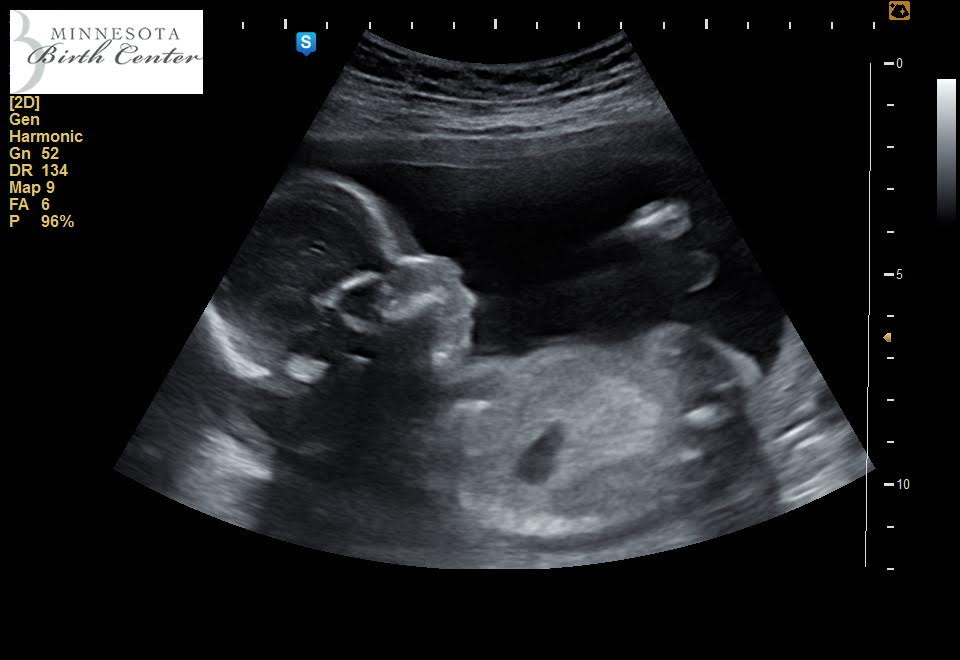

Brave Bear Royer

Celebrating our little girl!